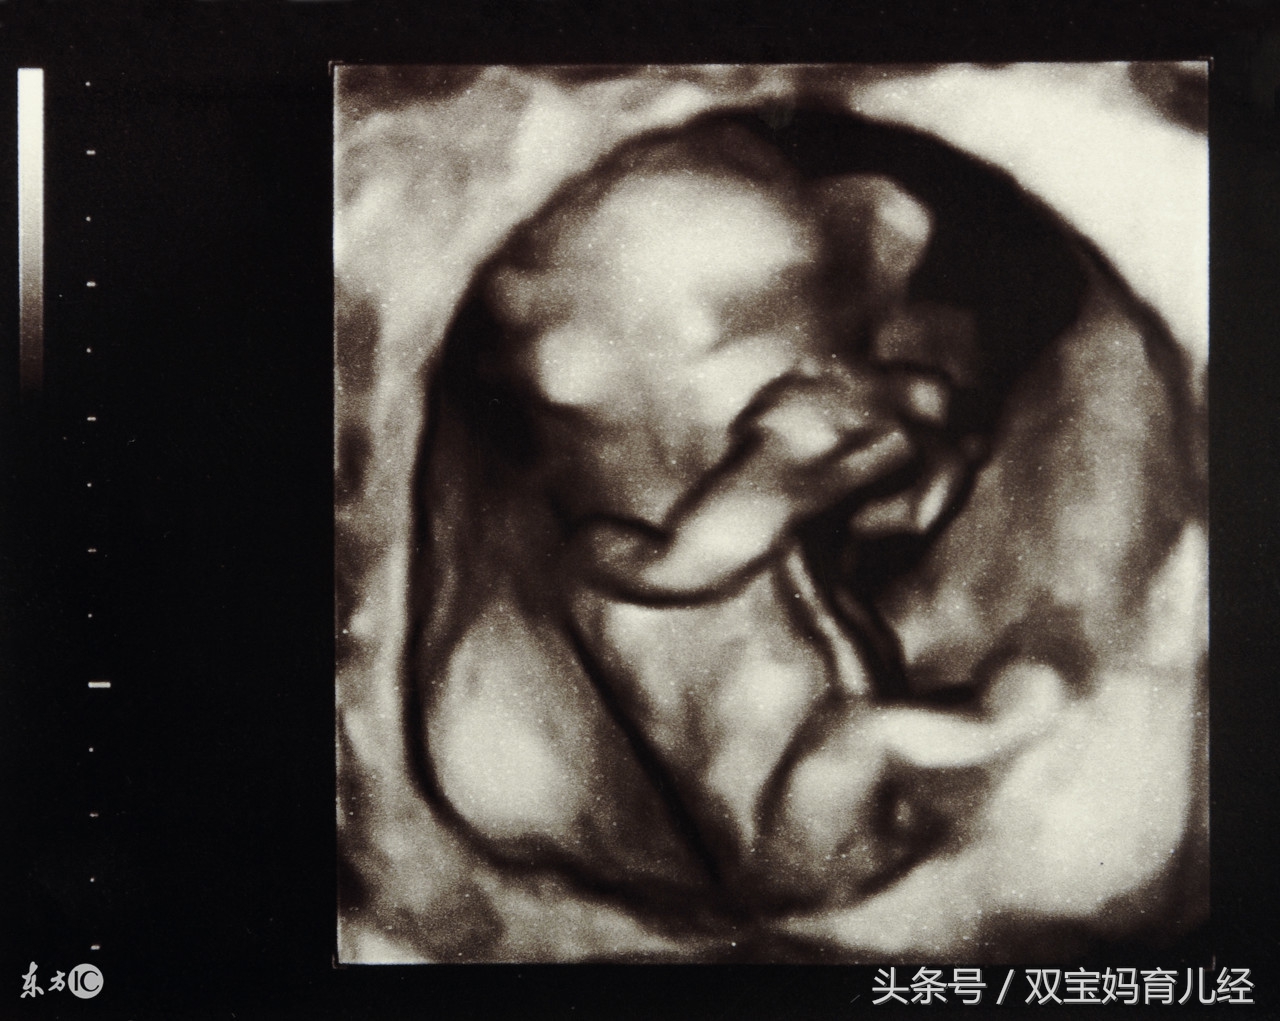

到了医院,医生马上安排了B超检查,惊奇地发现肚子里的宝宝一只脚已经伸到了子宫外!孕周增大,肚子里的宝宝活动太频繁,一脚把玲姐的子宫给踢破了!

在孕22~25周进行系统B超检查时就应明确胎盘位置及其与瘢痕的关系,对可疑患者应于孕28~30周复查胎盘位置,超声多普勒检查是否有胎盘植入,必要时行MRI检查进一步明确诊断,并注意无痛性阴道流血情况。

从孕34周开始,应每周进行B超监测子宫下段的肌层变化,怀孕38周的时候就要住院监测子宫下段肌层厚度的变化。